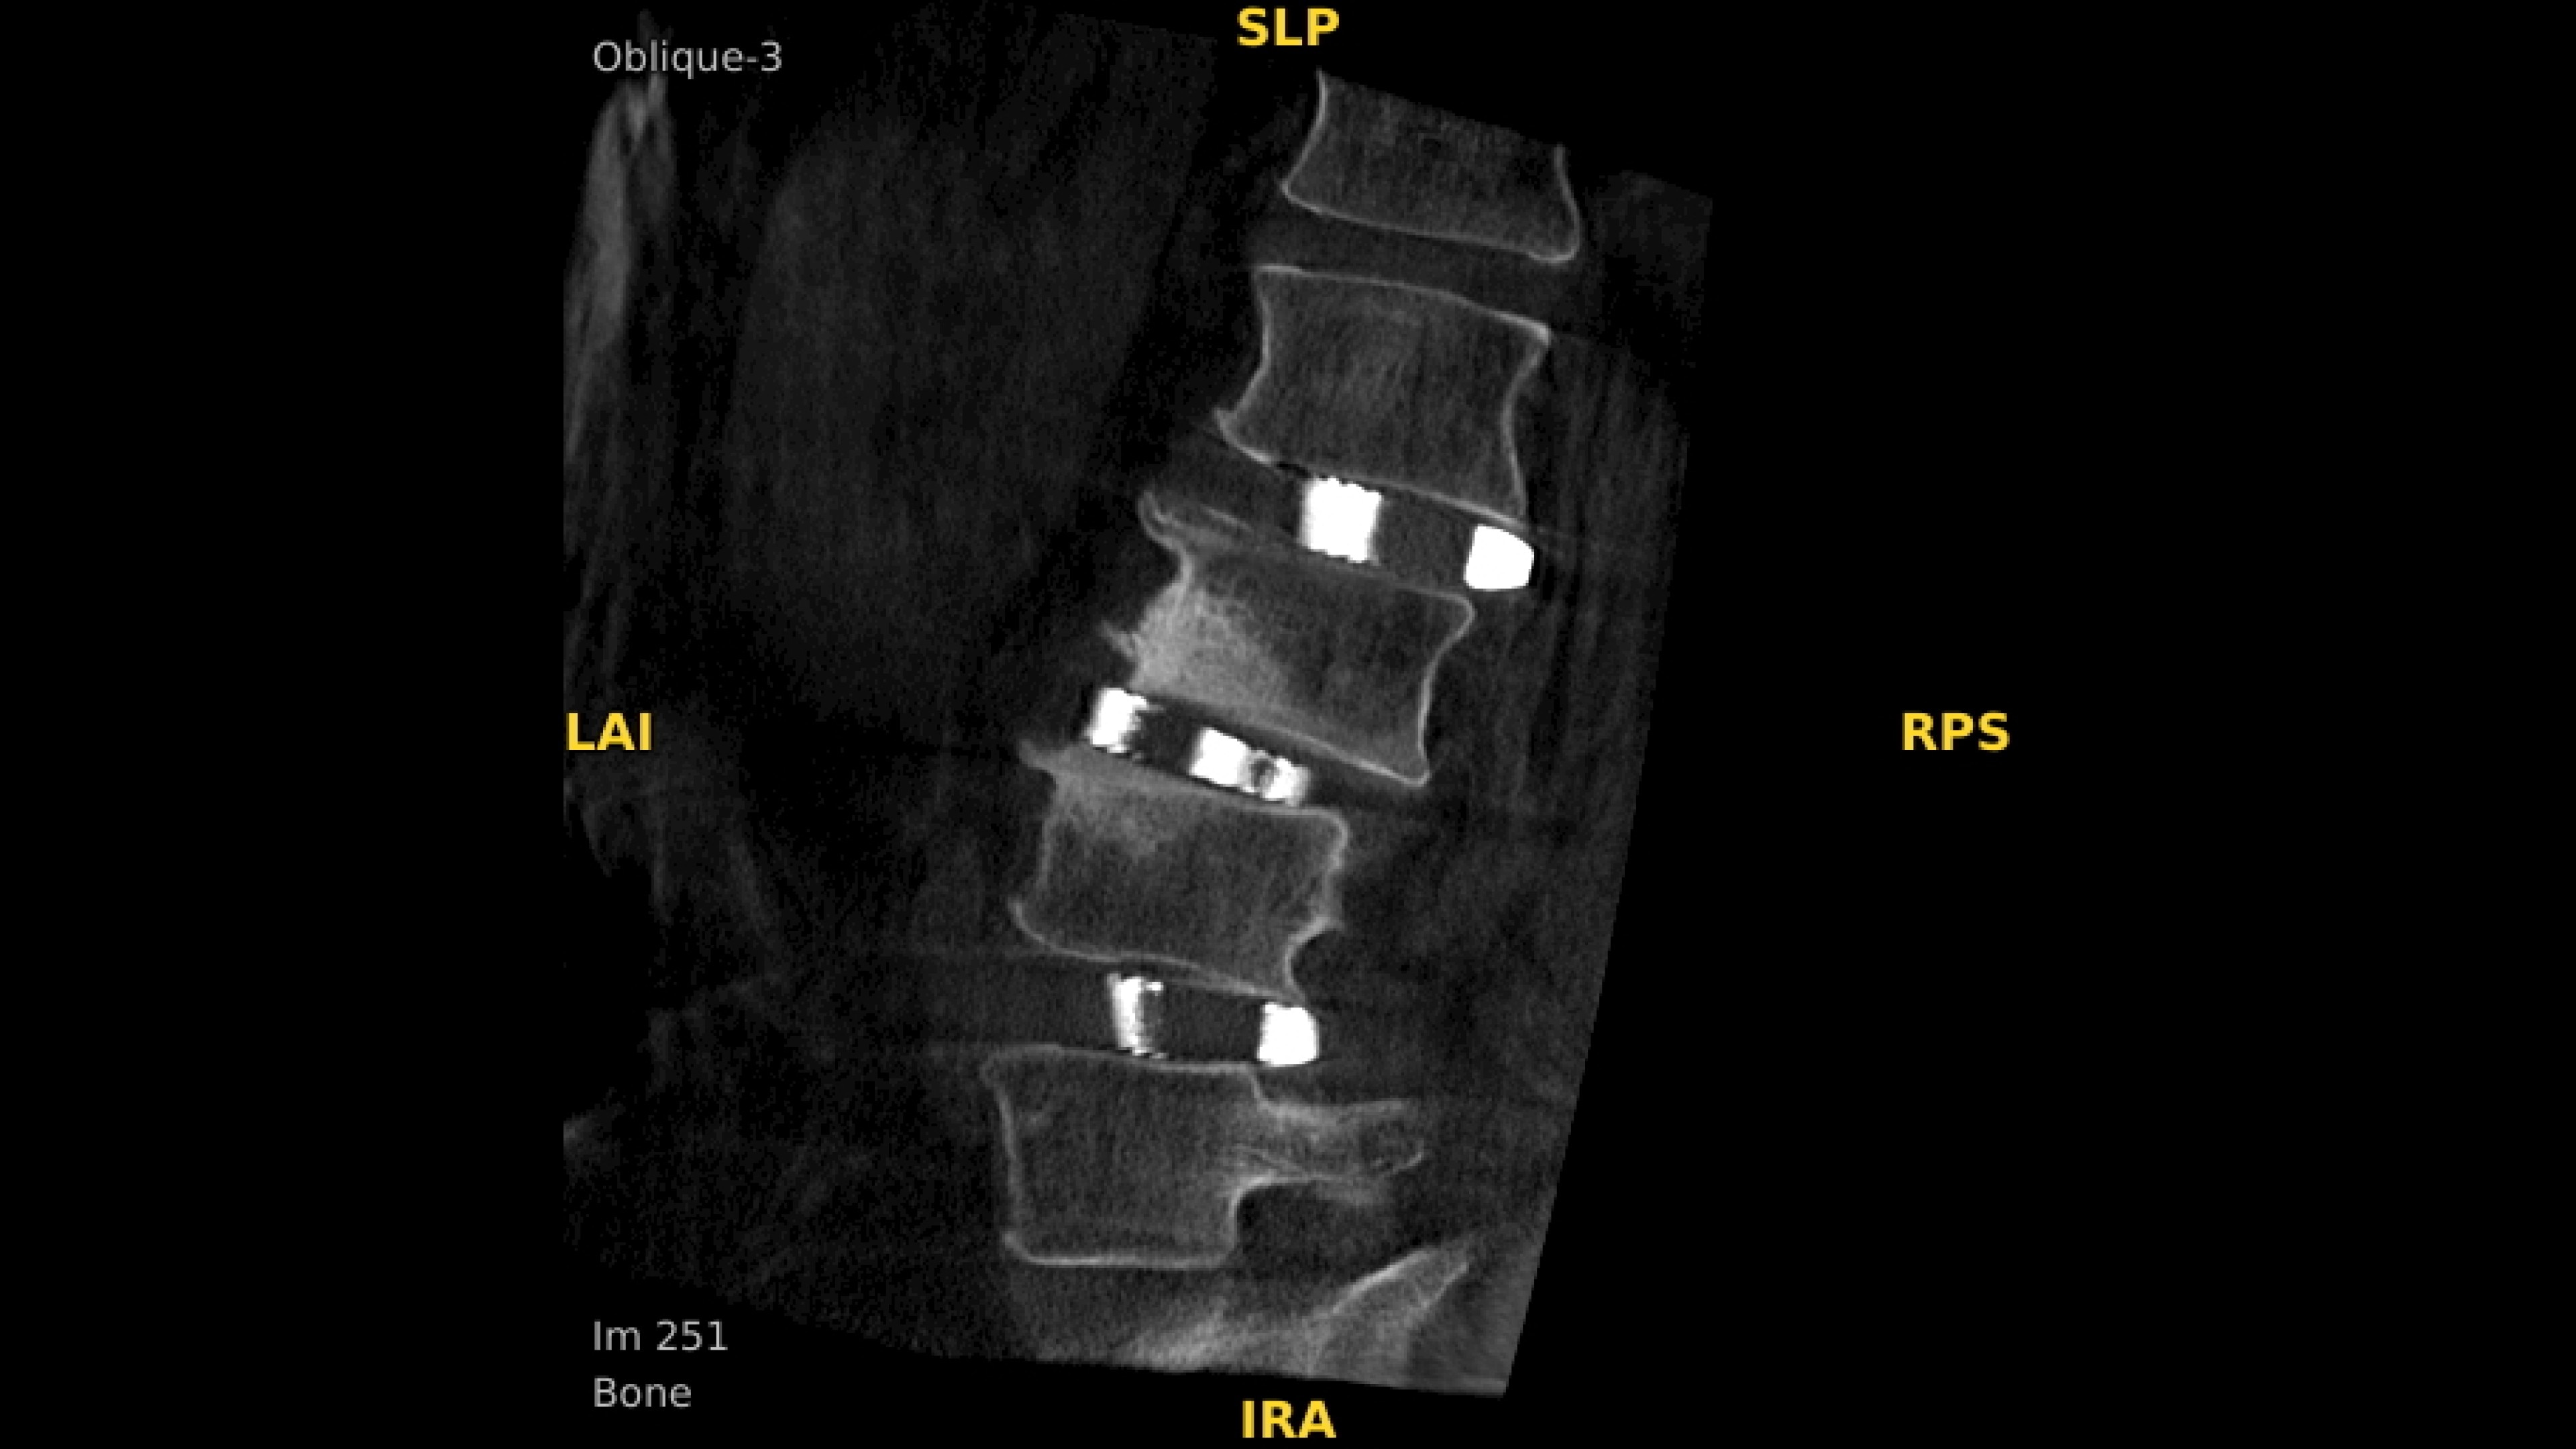

Analyze CT-like images with the OEC 3D Volume Viewer which includes Multi-Oblique, Area Measure, Window Level/Window Width, rotate, zoom, and more for quick and comprehensive visualization.

Review screws with automatic detection and numbering, manually label spine levels, and visualize spinal curvature alignment with Spine Suite, an optional application available with OEC 3D.